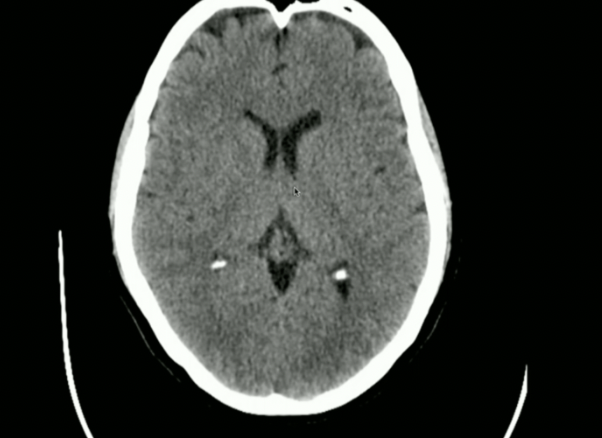

<p>Is this normal/abnormal?</p>

Is this normal/abnormal?

• Normal: the Choroid Plexus can Naturally Calcify